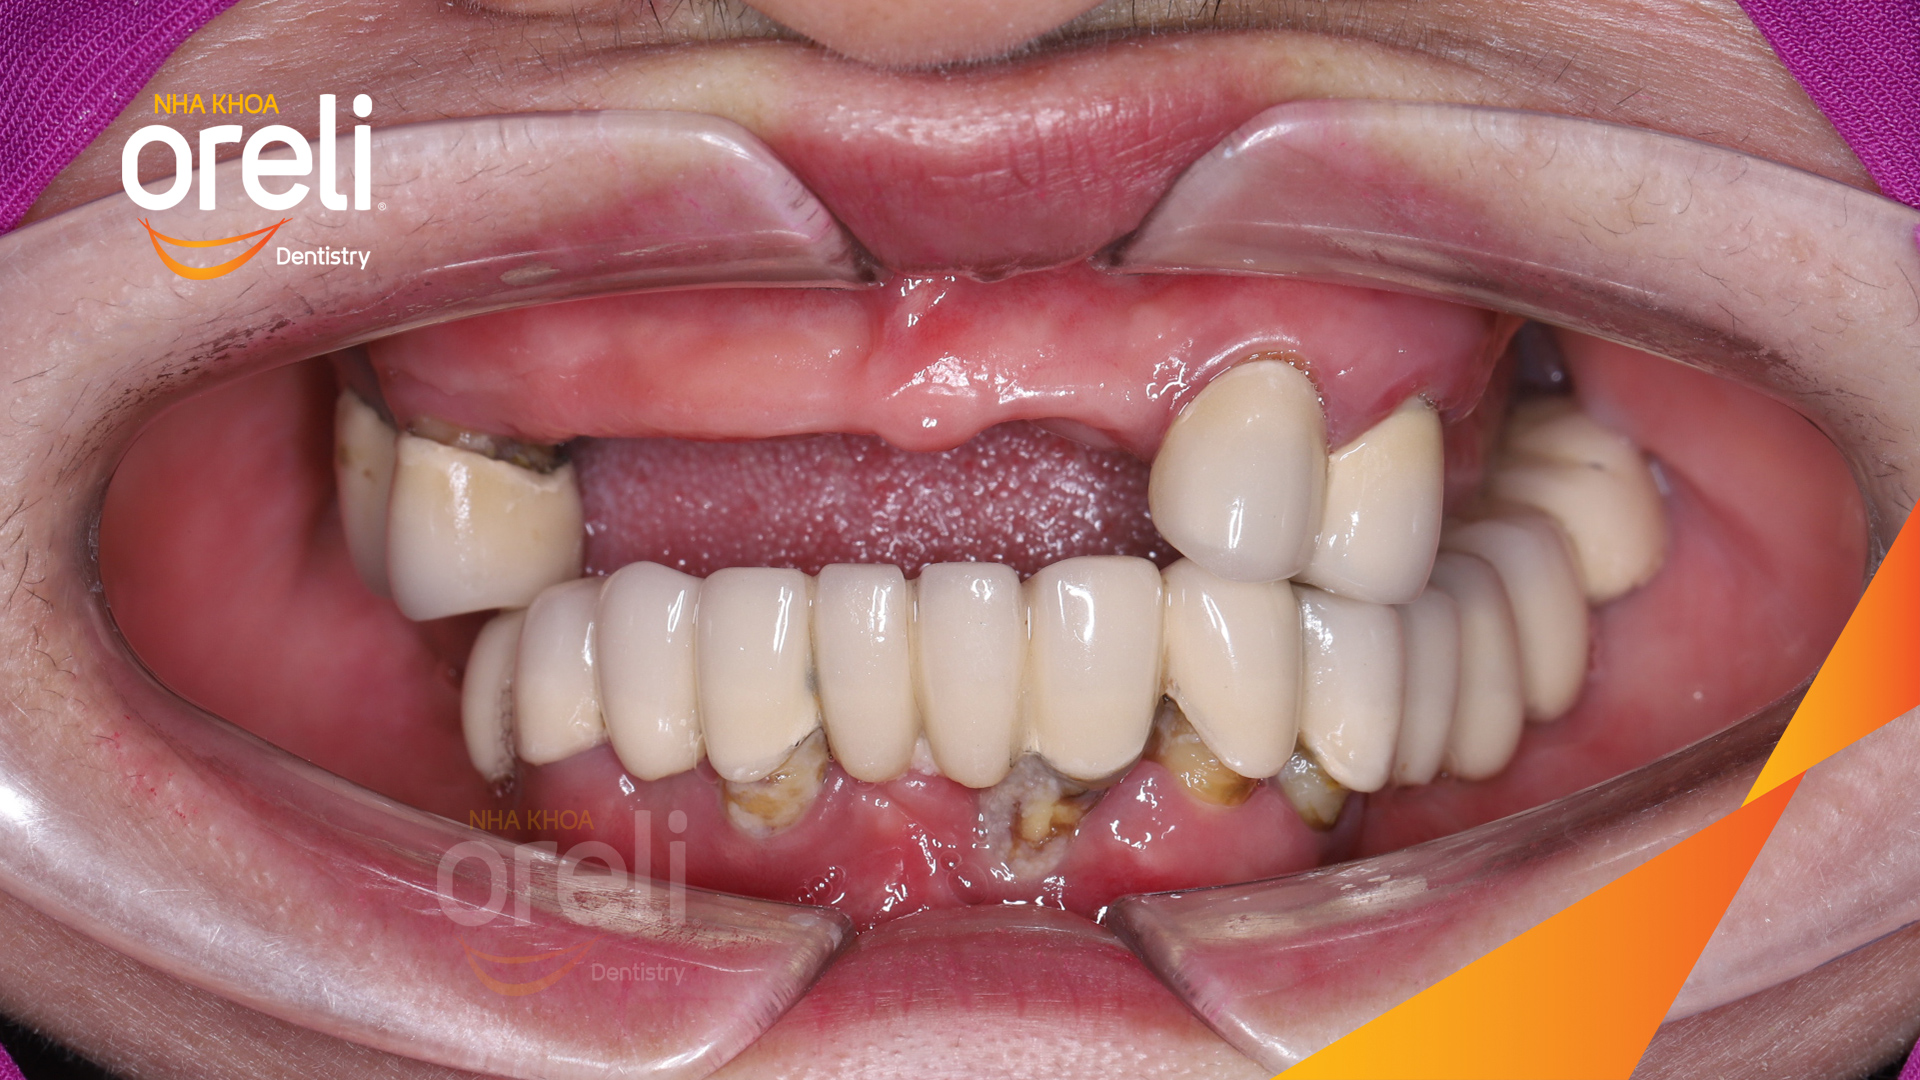

Tình trạng: Cầu răng sứ lâu ngày, tiêu xương nhiều ở cả hàm trên và dưới

Giải pháp: Cắt bỏ cầu sứ nhổ răng lung lay, cấy ghép răng implant hàm trên và dưới

Kết quả: Chị khách cười nói tự tin và ăn nhai chắc chắn

Hình ảnh thực tế